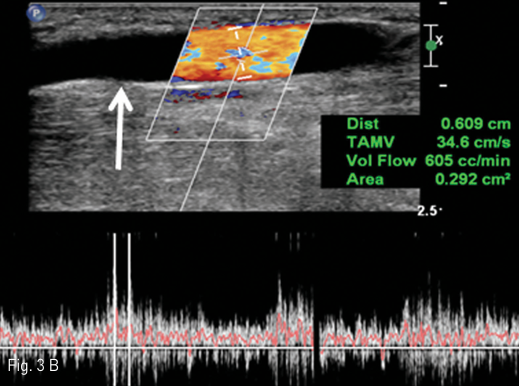

Fig 3B

B. The post-fistula cephalic on upper arm (arrow) is dilated to almost 6.1 mm diameter and a blood flow of the cephalic vein estimates 605 ml/min.